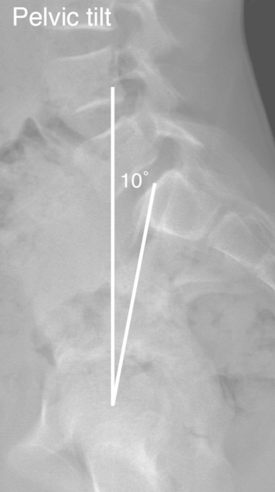

7

Q

Espondilolisteses

• Qual a definição e as principais características do Tilt Pélvico (TP)?

Depende da posição da pelve

A

• Ângulo entre a linha que liga o centro da cabeça femoral ao centro do platô de S1 e a linha perpendicular ao solo, passando pelo centro da cabeça femoral

• Pode ser alterado pela translação e retroversão pélvica

Quanto > o Tilt Pélvico (TP) > a retroversão da pelve

Bizu: Tilt → Teto (a linha vai para o teto)